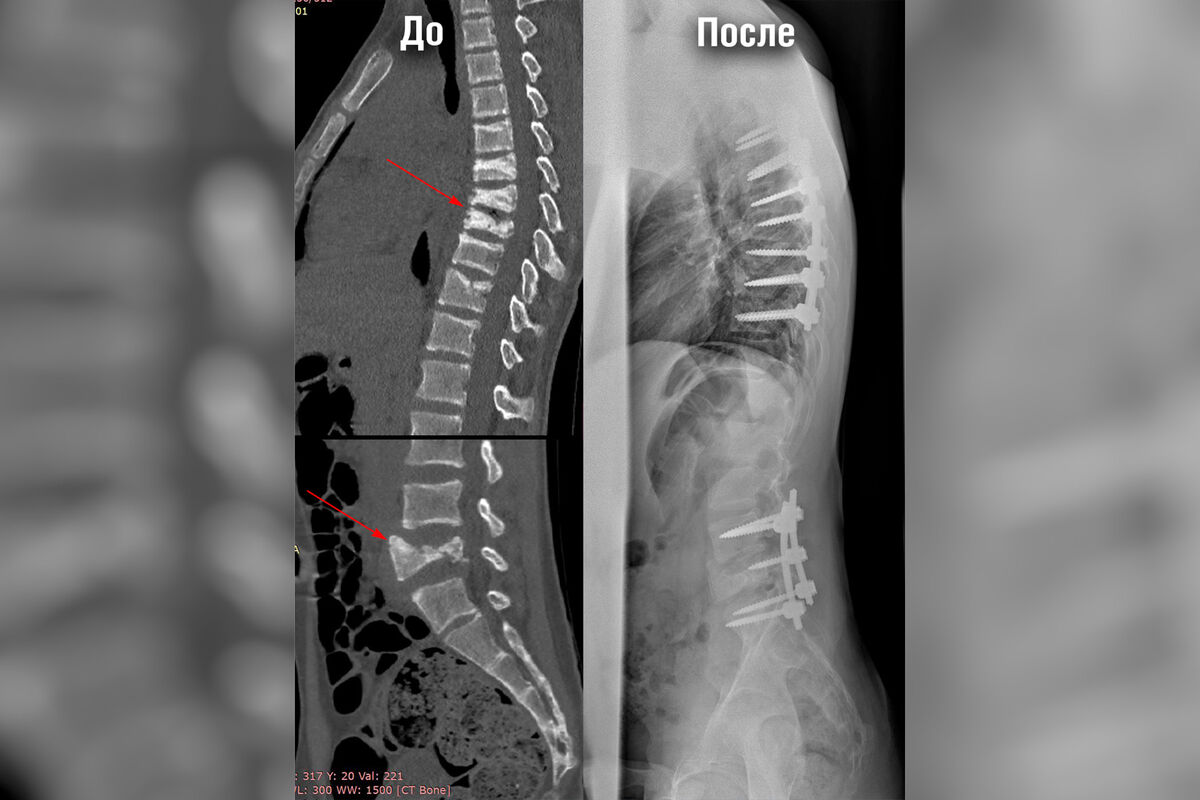

Мальчику провели комплекс обследований, в том числе КТ и МРТ позвоночника, по результатам которых врачи обнаружили компрессионные переломы позвонков в грудном и поясничном отделе. Для проведения экстренной операции по фиксации переломов врачам необходимо было стабилизировать состояние пациента.

Стандартным подходом к лечению компрессионных переломов позвоночника является транспедикулярная фиксация при помощи металлоконструкции — сложная высокотехнологичная операция.

«Мы получили доступ к области переломов, установили в тела позвонков специальные винты, после чего соединили их стержнями. Всего было установлено две металлоконструкции — протяженностью в семь позвонков грудного отдела и в три позвонка поясничного. Затем мы уложили их костным аутотрансплантатом, чтобы обеспечить максимальную стабильность в дальнейшем», — рассказал о ходе оперативного вмешательства Андрей Пантелеев.